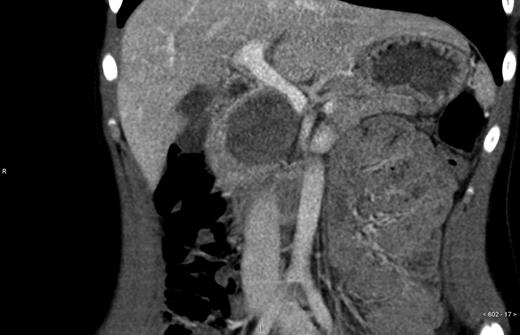

An otherwise healthy 14-year-old girl was referred to the Department of surgery Uppsala University Hospital from another hospital where she underwent a trauma-CT after receiving an elbow to the abdomen during a basketball game. The CT displayed no signs of traumatic injury, but revealed a 6.5 × 4.5 × 5.0 cm large tumor in the pancreatic head (Figs 1 and 2) which displaced the portal vein, vena cava and hepatic artery. Further investigation revealed that the patient had felt tired and had lost some weight during the past 6 months. Contrast-enhanced ultrasound with Doppler indicated a tumor with both solid and cystic structures, but no signs of vascular encapsulation. The investigation was complemented with positron emission tomography, hormone screening and an ultrasound of the heart. On the contrast-enhanced ultrasound the tumor appeared resectable; therefore no endoscopic ultrasound or biopsies were taken.

Radiologically, SPPT has known features. In CT, a well-defined heterogeneous tumor with both cystic and solid areas is observed, with the cystic areas being central and the soild areas being peripheral [8]. Calcification in the tumor has also been described [9].